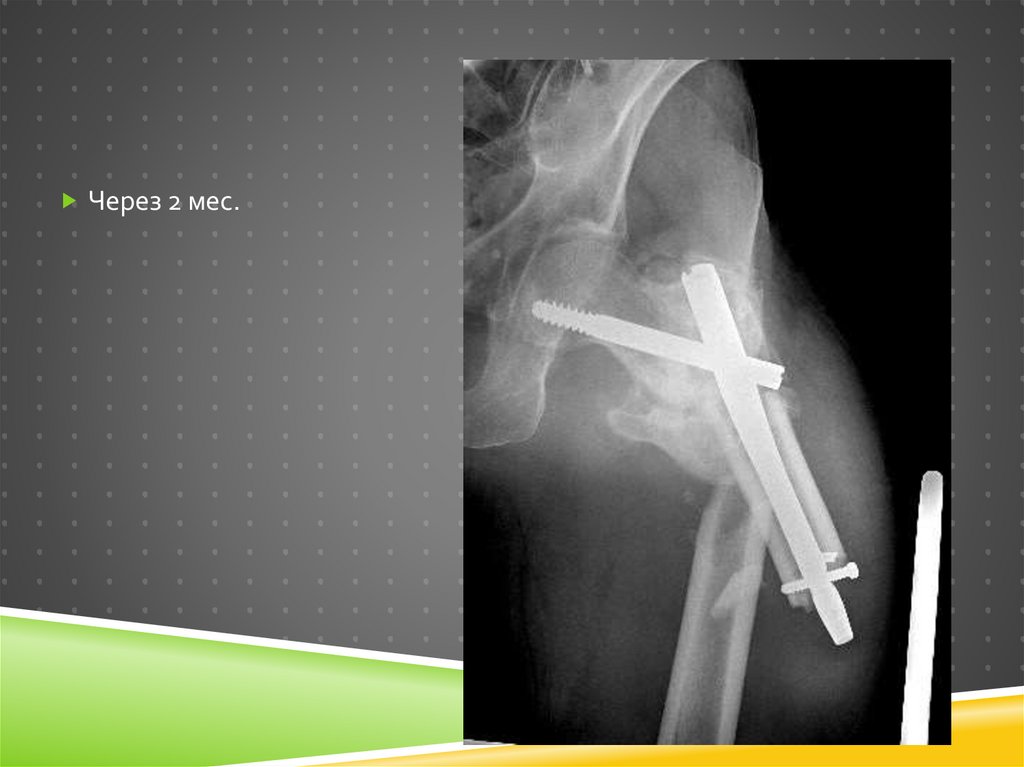

Через 2 мес.